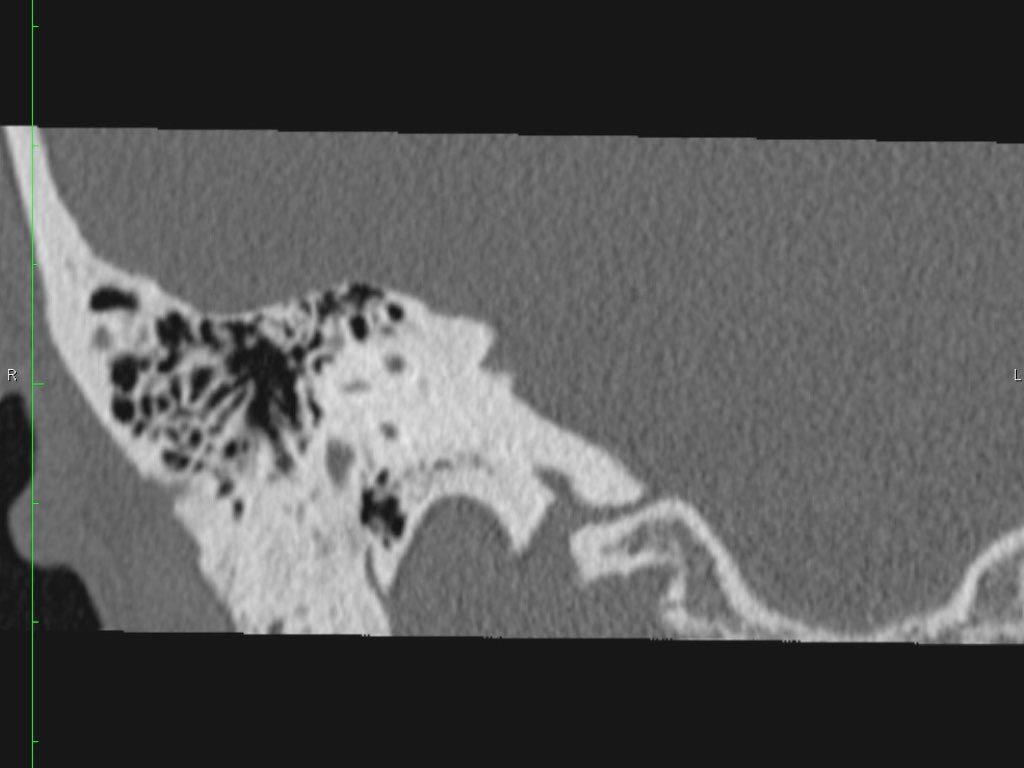

Giải phẫu mặt phẳng coronal của xương đá

Nhấp vào hình ảnh để phóng to.

Cuộn qua các hình ảnh.